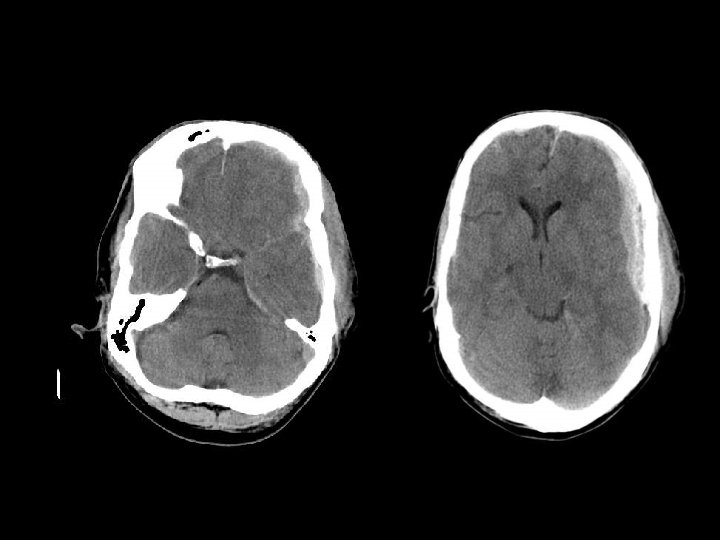

SUBDURAL HEMATOMA n Timbul antara dura dan arachnoid n Dapat melewati sutura n Timbul akibat disrupsi bridging cortical veins n Bentuk konkaf n Hipodens(hiperakut, kronis), isodens(subakut), hiperdens(akut)

W=33 L=41

PENANGANAN SDH n SDH akut dengan ketebalan > 10 mm atau pergeseran midline > 5 mm harus dievakuasi n Pasien yang koma dengan penurunan GCS >2 poin dengan SDH harus menjalani operasi evakuasi